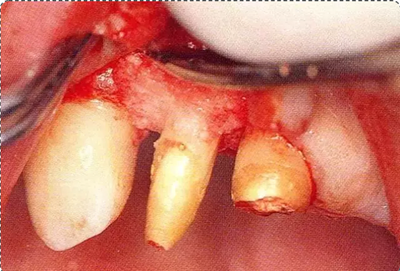

圖10-4  骨缺損部位進(jìn)行骨修整結(jié)束的狀態(tài)。